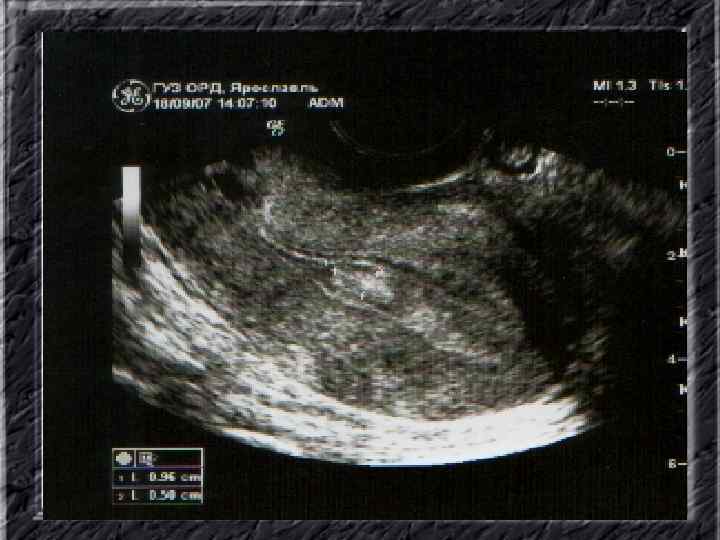

Названия слайдов: • • • • Слайд 61. Лапароскопия: множественные спайки в полости малого таза женщины. Слайд 62. Лапароскопия: признаки спаечной болезни в полости малого таза женщины. Слайд 63. Лапароскопия: деформация маточной трубы при спаечном процессе в полости малого таза. Слайд 64. Ультрасонография: спаечный процесс в малом тазу. Слайд 65. Ультрасонография: мультифолликулярные яичники. Слайд 66. Ультрасонография: кистома яичника. Слайд 67. Ультрасонография: патолоргия эндометрия. Слайд 68. Ультрасонография: внематочная беременность. Слайд 69. Ультрасонография: внематочная беременность. Слайд 70. Кольпоскопия: кандлилома – папиллома. Слайд 71. Кольпоскопия: кандлидозные бели. Слайд 72. Кольпоскопия: полип шейки матки. Слайд 73. Кольпоскопия: эрозия шейки матки. Слайд 74. Кольпоскопия: экспульсия ВМС.